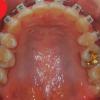

[치아교정후기27] 교정만의 오라픽스 치아교정후기 - 위 아래 철사 감았어요~

[치아교정후기27] 교정만의 오라픽스 치아교정후기 - 위 아래 철사 감았어요~ 안녕하세...

[치아교정후기26] 교정만의 오라픽스 치아교정후기 - 잘때만 고무줄

[치아교정후기26] 교정만의 오라픽스 치아교정후기 - 잘때만 고무줄 캬하하하 여러분 ...